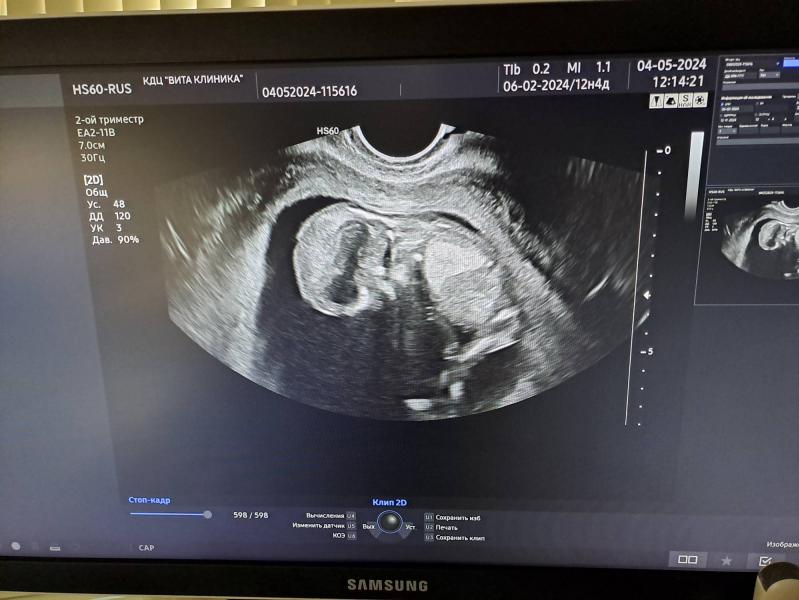

А еще, ходили в субботу на узи.

Срок ровно на неделю больше, чем по месячным.

Кто там - не понятно.

Руками-ногами машет, головой шевелит, сам вилькается🙃

Пытались словить "добро", не смогли.

Но вроде как всамом начале, чтото и заметно было. Так что, наш интригант-малыш, пока неизвестен😅